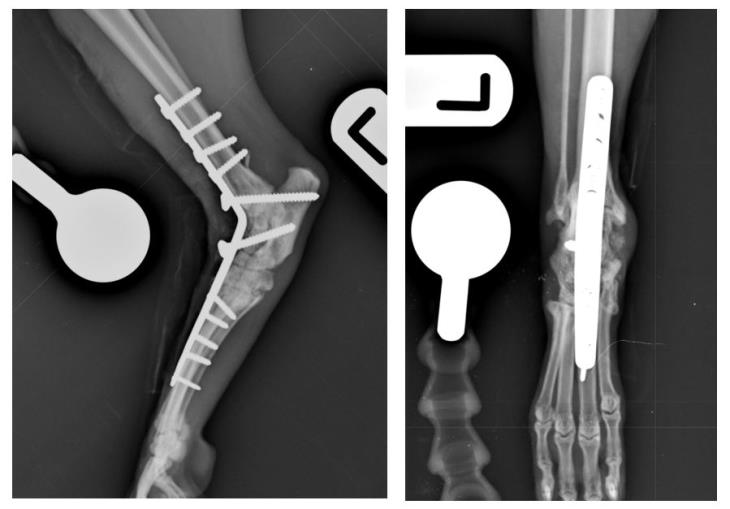

The procedure is carried out using a specifically designed bone plate contoured to the shape and angle of the cat’s tarsus and accepting screws of different sizes to match the underlying bone thickness.

The radiograph below shows a postoperative view of this patient’s left tarsus after having been stabilised with a plate.